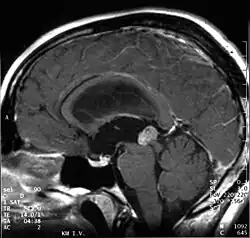

Papillary tumors of the pineal region were first described by A. Jouvet et al. in 2003[1] and were introduced in the World Health Organization (WHO) classification of central nervous system in 2007.[2] Papillary Tumors of the Pineal Region are located on the pineal gland which is located in the center of the brain. The pineal gland is located on roof of the diencephalon. It is a cone-shaped structure dorsal to the midbrain tectum.[3] The tumor appears to be derived from the specialized ependymal cells of the subcommissural organ.[1][4][5] Papillary tumors of the central nervous system and particularly of the pineal region are very rare and so diagnosing them is extremely difficult.[6]

Papillary tumors of the pineal region are normally well circumscribed. They are reported to be fairly large ranging between 2.5 and 4.0 centimeters. These tumors sometimes feature a cystic component.[13]